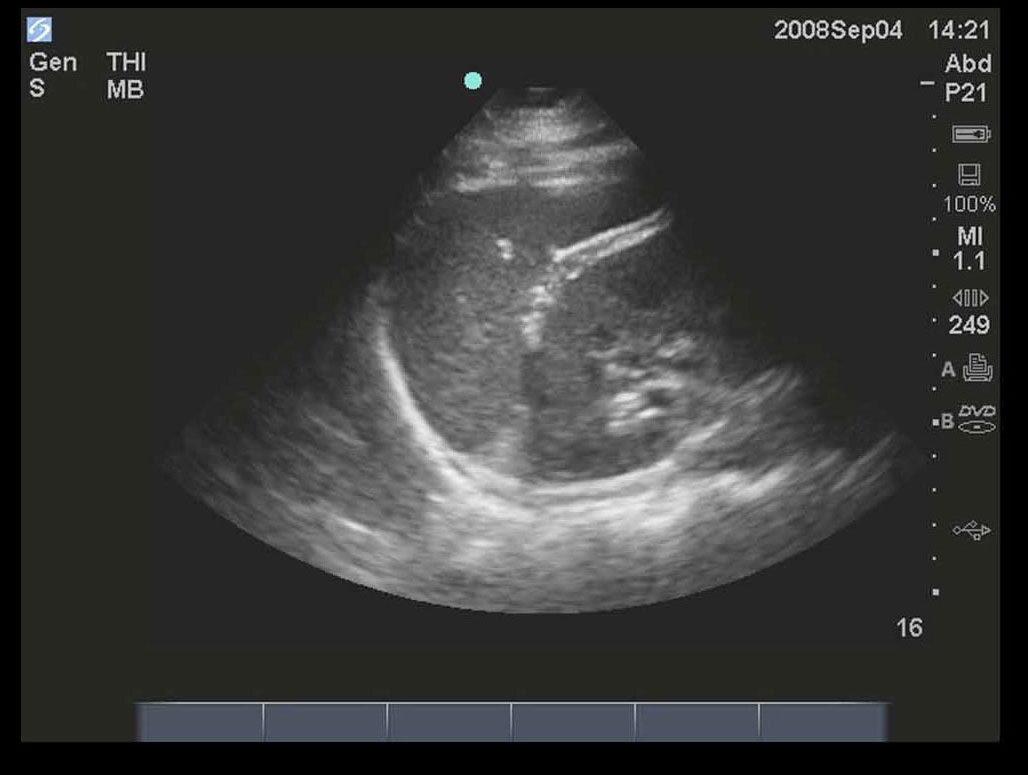

FAST 左上四半部 (LUQ) 1 画像

M-Turbo: FAST検査、左上四半部 1。